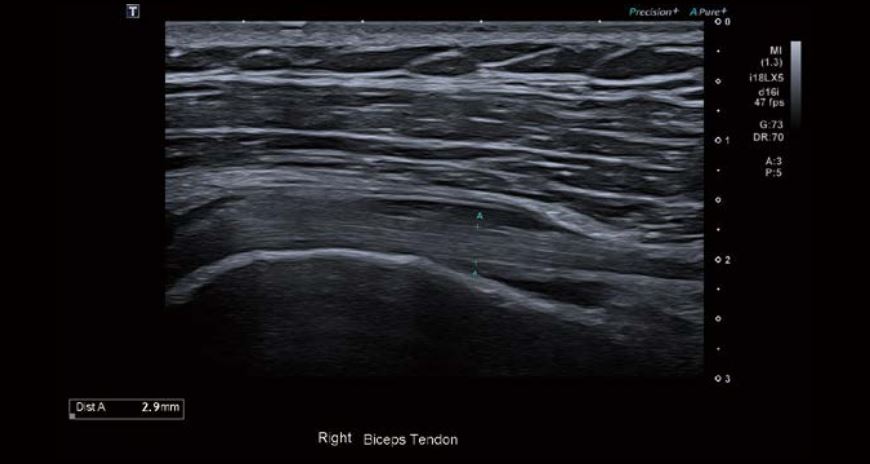

Було виявлено невеликий набряк оболонки сухожилля малого біцепса, потовщення та помірну васкуляризацію проміжку обертальної манжети. Спостерігалося незначне потовщення та асиметрія правої нижньої плечової зв'язки (НПЗ) та підпахвинної западини порівняно з лівою стороною. Товщина суглобової сумки була в межах норми, а в сухожиллях обертальної манжети спостерігалися мінімальні вікові зміни.

Зображення 1 Поперечне зображення сухожилля біцепса з використанням iBeam+ та Full Focus - видно рідину в оточуючій оболонці.